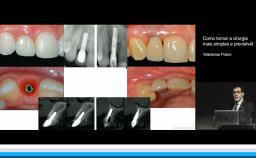

Apresentação traz uma revisão teórica sobre o potencial e previsibilidade dos implantes curtos ilustrados com uma série de casos desafiadores, com o objetivo de simplificar a técnica cirúrgica e protética com segurança e resultados previsíveis. Os casos apresentados trazem uma discussão clínica sobre as indicações, possíveis motivos de falhas e sugestões de soluções para casos limites e complexos.